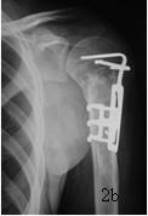

Figure 2. Female,15 years old. a. The AP plate of shoulder joint 30 days after injury shows the fracture of proximal humerus of  Neer Ⅵ .b. The oboslete fracture of anatomical neck and dislocation of caput humeralis.There is 3.7cm's displacement between ends of fractured bone.